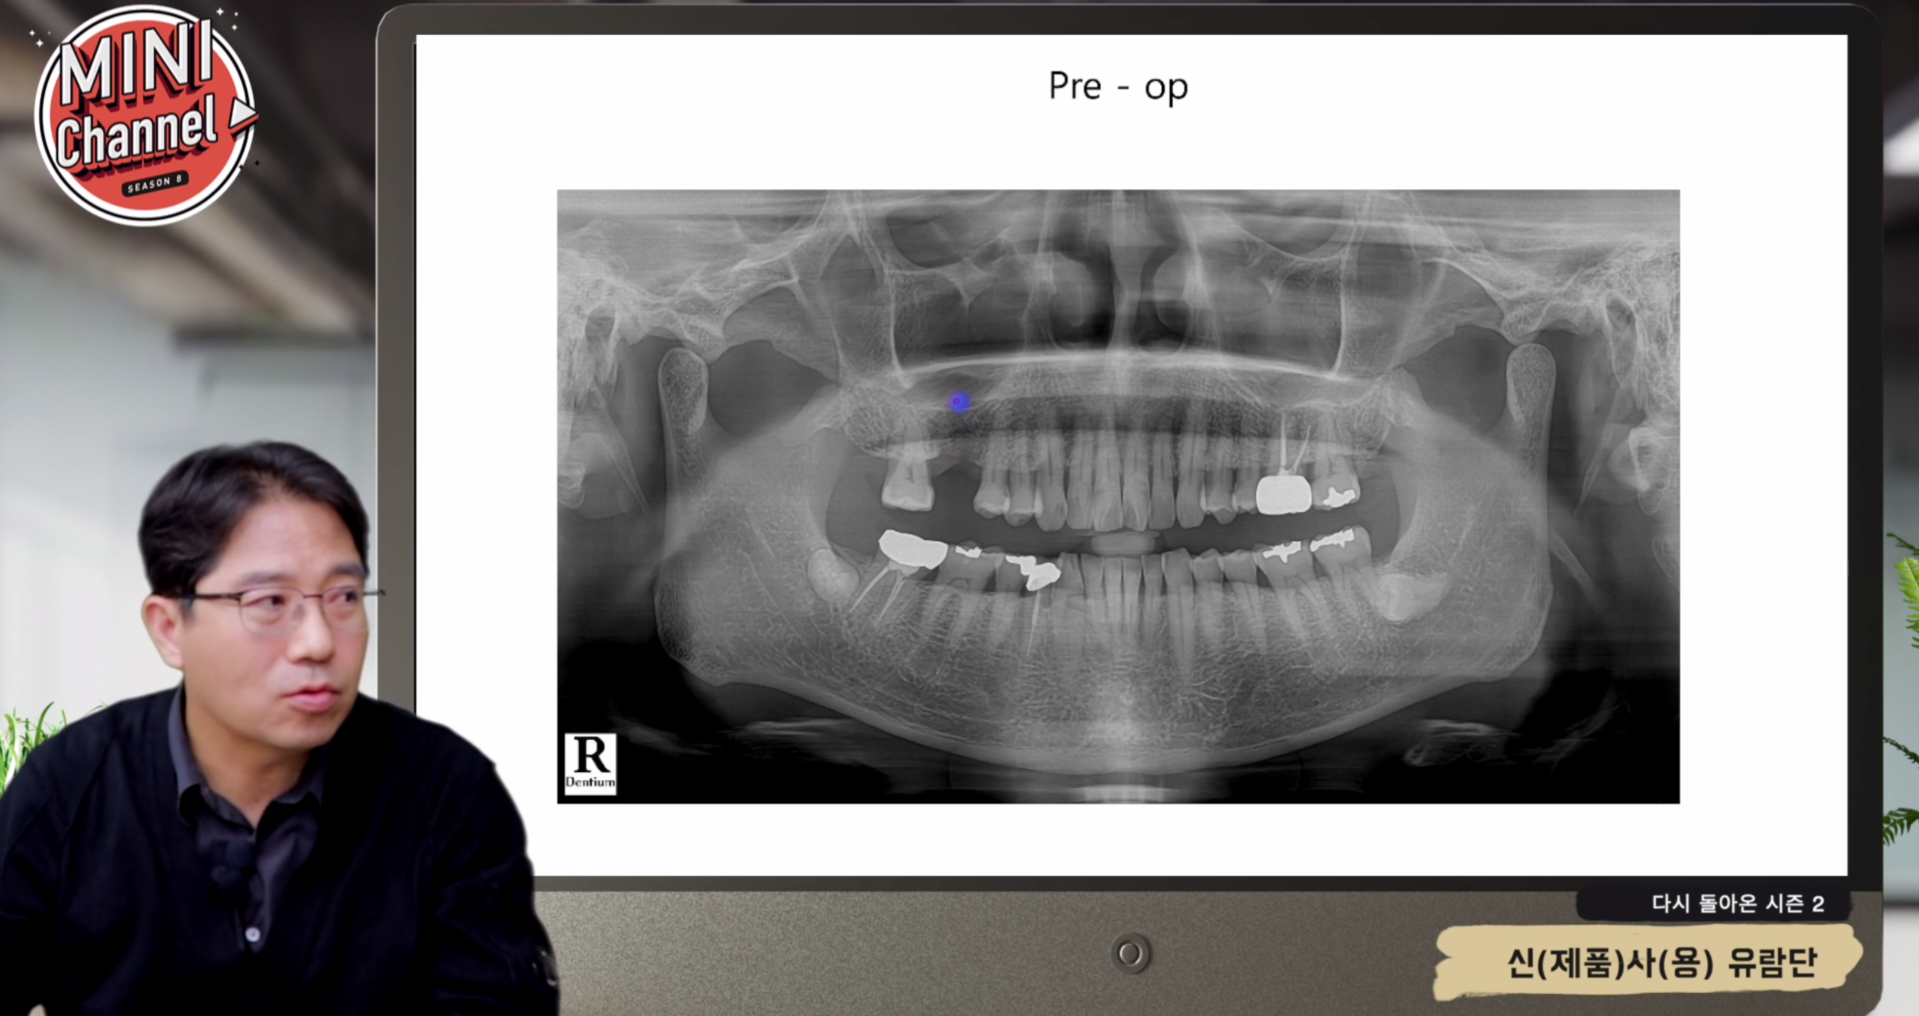

SES KIT 증례에서는 잔존골이 충분치 않은 케이스에서도 크레스타 접근으로 즉시 식립 + 동시거상을 반복해서 보여준다. 수술 직후 파노라마/CT와 3개월·6개월 추적 영상에서 dome 형태가 크게 변형되지 않고 유지되는 것이 인상적이다.

단순히 "막을 안 찢었다"가 아니라, 골과 이식재가 섞이면서 안정적으로 성숙하는 모습까지 데이터를 통해 확인할 수 있다는 점이 이 강의의 큰 장점이다.

SES KIT 동시거상 수술 직후 CT SES KIT 동시거상 추적 CT

▲ 동시거상 직후 vs 추적 CT